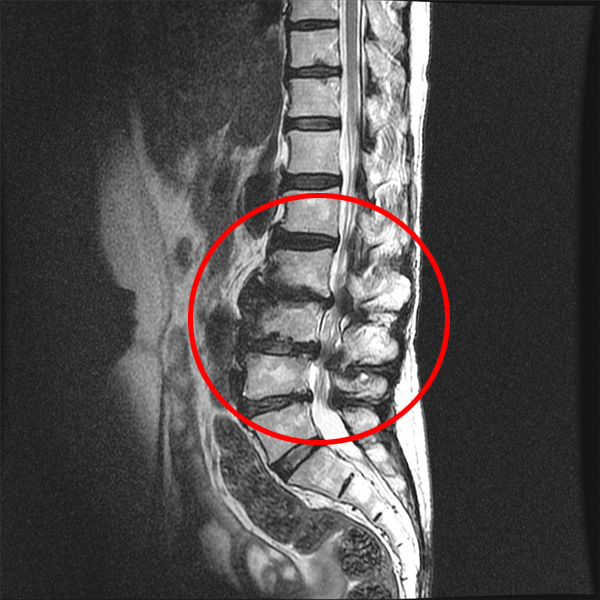

척추관협착증 환자의 MRI

앞서 유합술을 하게 되면, 뼈가 유합된 위아래 마디가 가장 큰 스트레스를 받는다고 설명 드렸습니다. 만약 인접한 마디가 젊고 건강하다면 움직임이나 충격을 받아도 당분간은 그리 큰 문제가 되지 않겠지만, 유합술을 받는 주변 부위의 퇴행이 이미 심하다면 그 유합된 부위로부터 넘어오는 스트레스나 압력을 견디지 못할 것입니다.

협착증은 여러 레벨에 걸쳐 퇴행이 진행된 상태이기 때문에 어느 특정 부위를 유합한다 해도 이미 퇴행되어 약해진 위아래 인접 마디가 움직임이나 충격을 견디기가 힘이 들 것입니다. 그래서 협착증 환자는 수술 이전에 유합술 이후 생길 수 있는 인접분절질환에 대해 충분히 알고 있어야 하며, 척추협착증수술을 진행하는 병원 역시 환자에게 수술 이후 인접분절질환의 발생 가능성과 예방법에 대해 철저히 교육해줄 필요가 있습니다.